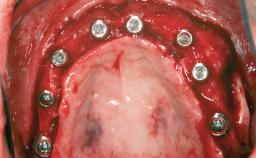

A 45-year-old woman with a completely edentulous maxilla was referred to evaluate the possibility of rehabilitation with an implant-supported prosthesis. This patient was healthy and a non-smoker. She had been wearing a maxillary complete denture opposing a natural mandibular dentition since her twenties. This situation had resulted in progressive resorption of the alveolar ridge, repeatedly creating a need for relining the denture. Twenty years later, despite multiple adaptations and the use of “glues” the denture was unstable and causing the patient psychological and functional discomfort.

# of Implants 8

Type of Implants Reduced-Diameter|Two-Piece

Bone Augmentation Horizontal|Sinus Floor Elevation|Staged|Vertical

Augmentation Materials Autogenous chips|Autogenous block(s)

Defining Characteristics Fully edentulous upper jaw to be rehabilitated with four or more implants

Modality Fixed hybrid bridge on 5+ implants

Bone Volume Deficient vertically or deficient vertically AND horizontally